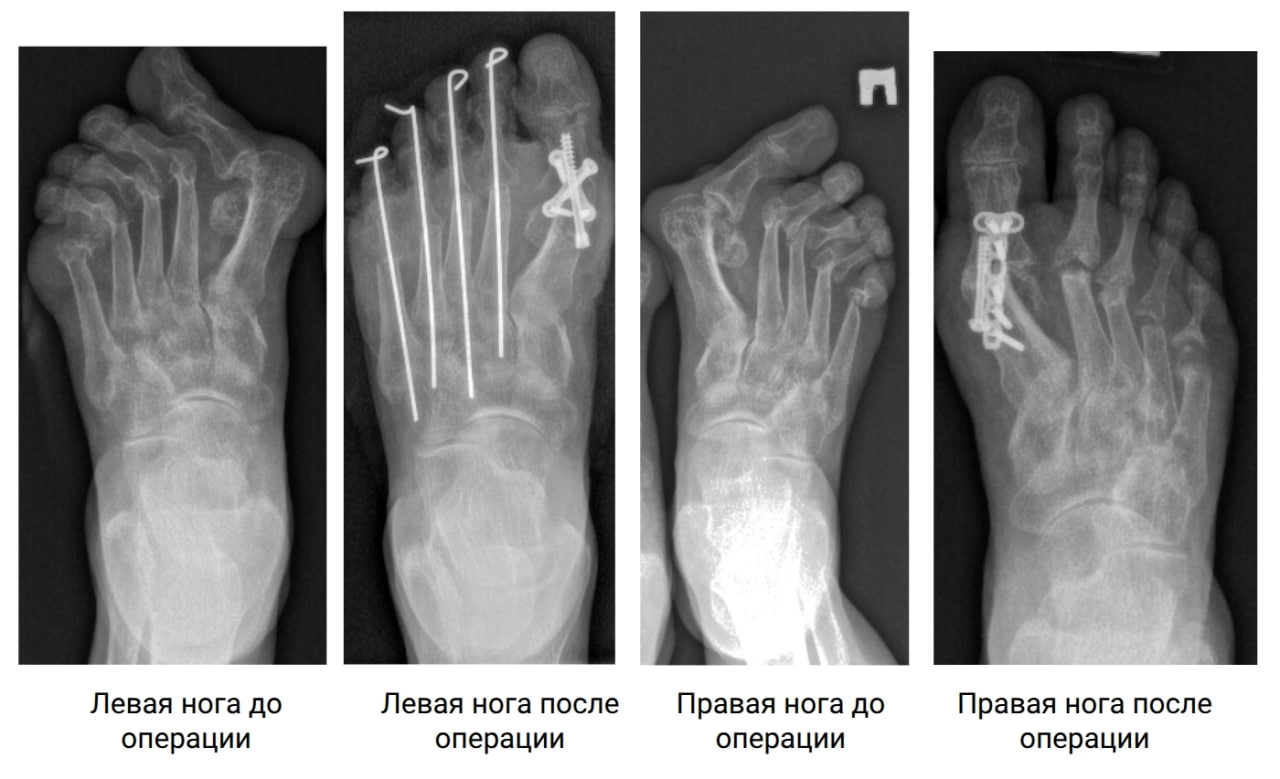

За 20 лет болезнь сильно деформировала стопы. Елене пришлось сменить привычный 38-й размер обуви на 41-й — из-за ширины стопы.

На помощь пришли специалисты ННИИТО им. Я.Л. Цивьяна. Ситуация была сложной: из-за артрита головки плюсневых костей были практически разрушены.

Операции проводили в два этапа: сначала на правой ноге (она болела сильнее), а через некоторое время — на левой. Врачи буквально «пересобрали» стопы, вернув пальцы в правильное положение.

После восстановительного периода Елена наконец-то смогла вернуться к обычной жизни. Теперь она ходит в привычной обуви и, самое главное, — без боли!